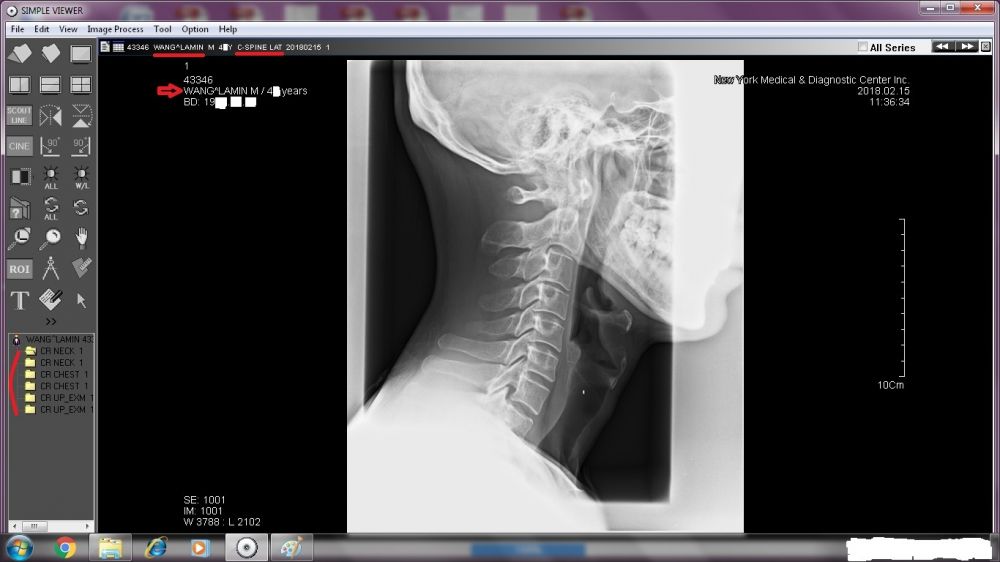

A TREMENDOUS amount needs to be revealed. Right now, I will start with the two sets of X-ray images done by New York Medical & Diagnostic Center (80-46 Kew Gardens Rd, Kew Garden, NY 11415. Tel: (718) 261-1000 ).